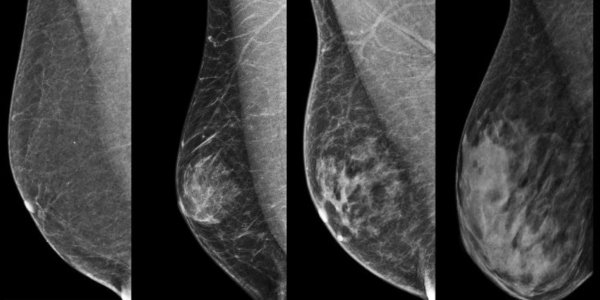

Should women be told about their high breast density as part of mammography screening? While this may sound like an obvious choice, a new study warns of unintended effects. |

Artificial intelligence is reshaping how clinicians identify women at higher risk of breast cancer – and may soon guide decisions on supplemental screening and treatment. At the European Society of Breast Imaging (EUSOBI) annual scientific meeting ... |